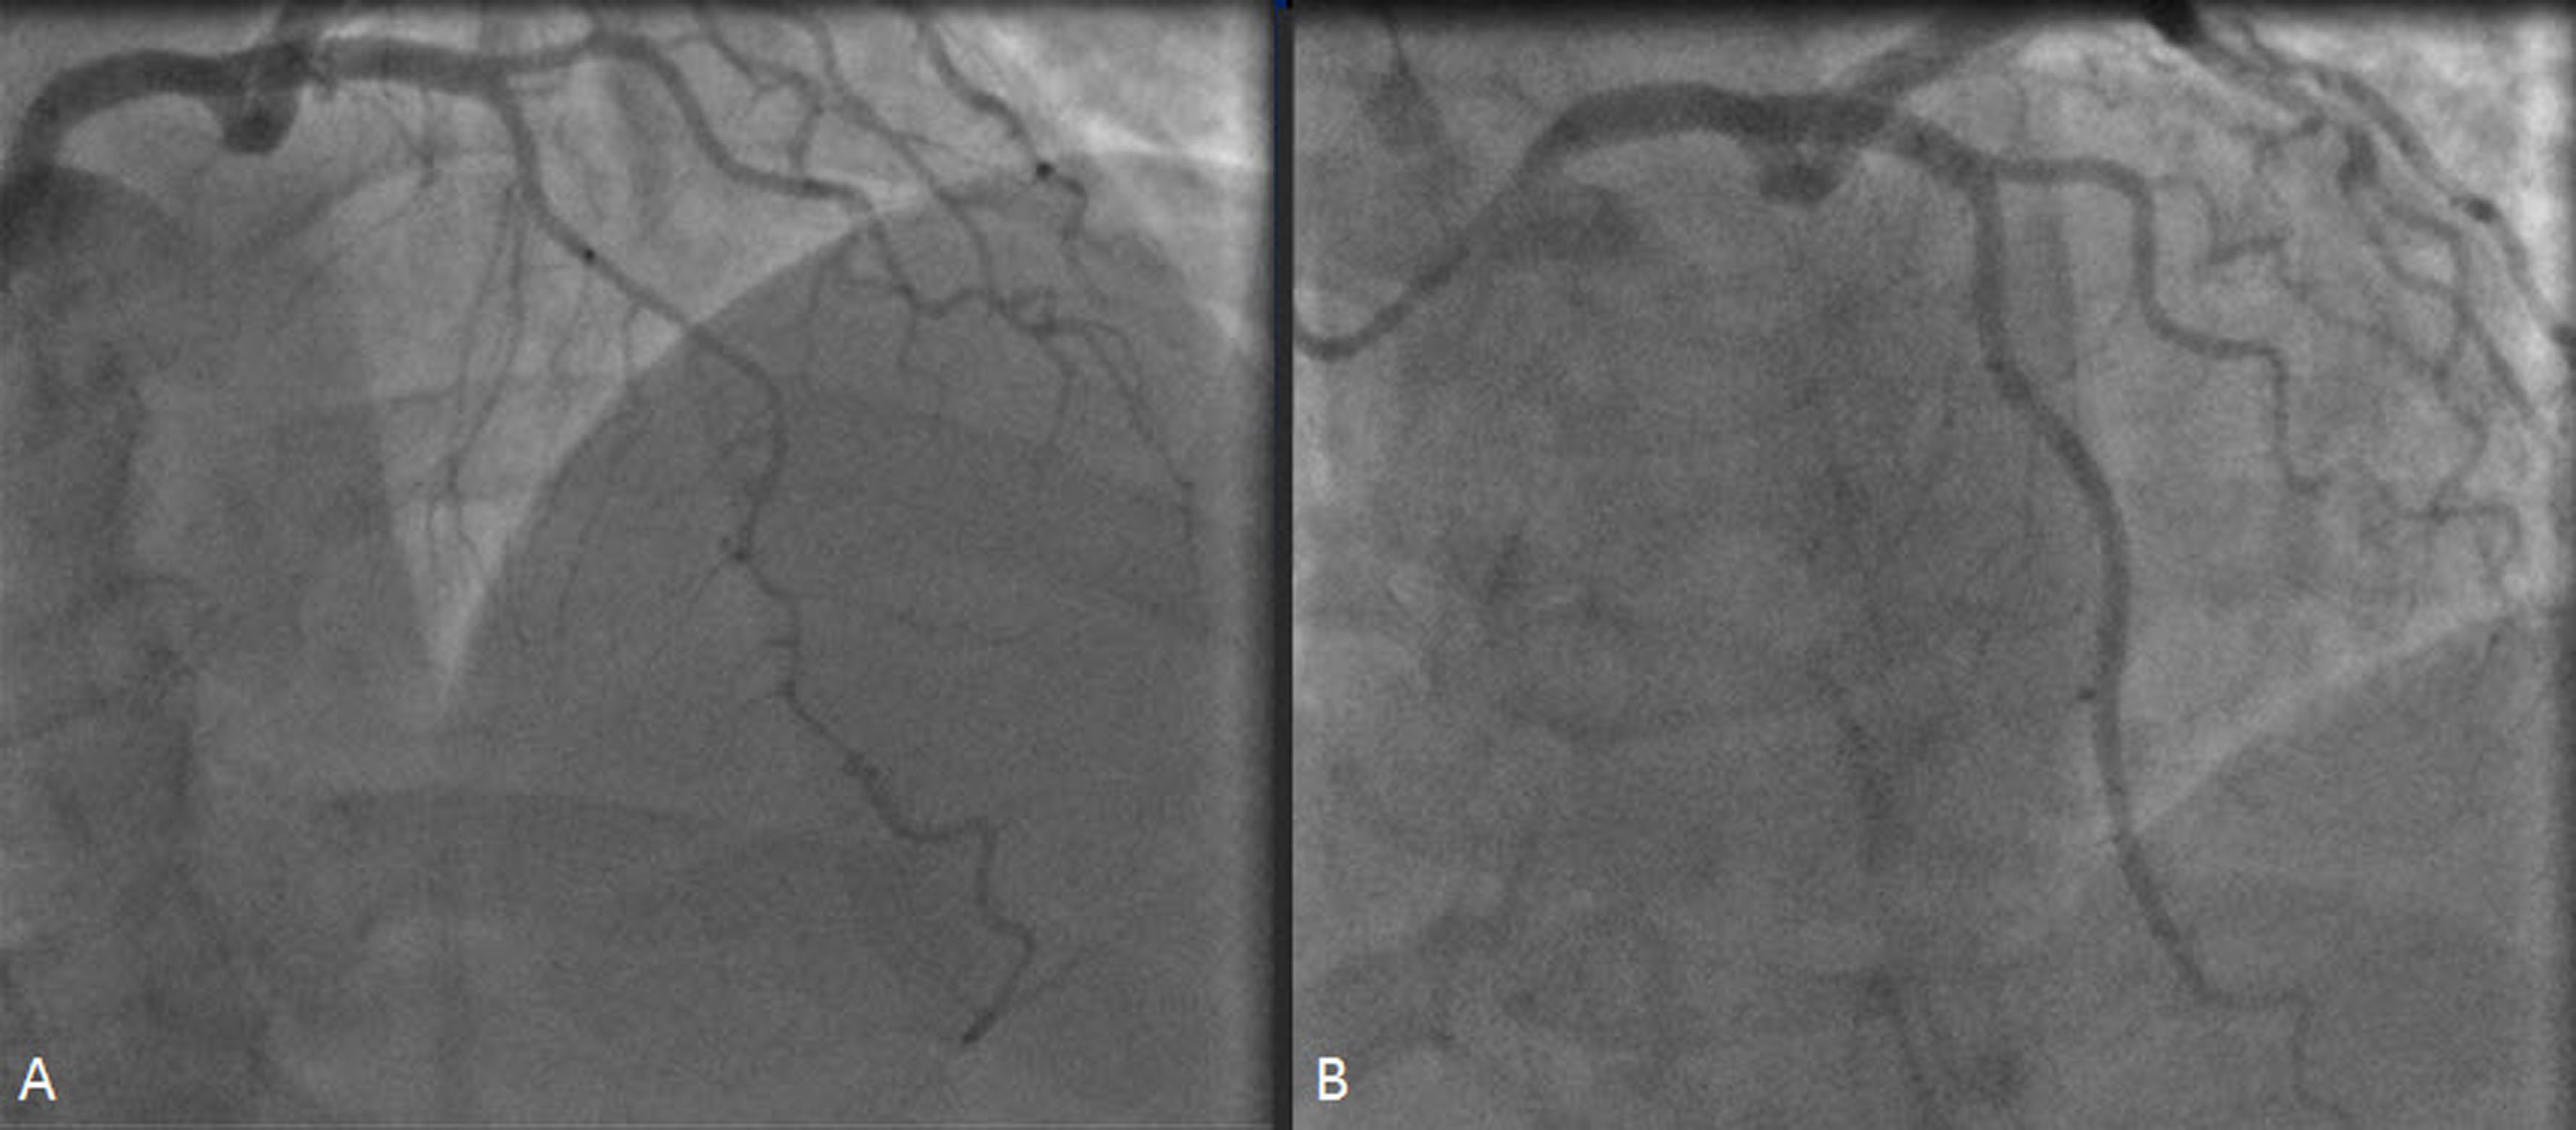

The treatment of long and diffuse coronary lesions with percutaneous coronary intervention (PCI) has been problematic since the era of plain balloon angioplasty. With the advent of bare-metal stents (BMS), long and multiple stents were used to completely cover the diseased segments in order to improve outcomes.  Lesion length has been proven to be a factor related to higher rates of restenosis and target lesion revascularization (TLR) and the risk was further increased by the multiplicity of implanted stents. Covering the lesion with the least number of non-overlapping stents might reduce the risk of restenosis. This strategy, called spot stenting, was initially tested in the BMS era to treat discrete high-grade disease within moderately diseased vessel segments and has been shown to significantly reduce restenosis rates. Drug-eluting stents (DES) have been consistently shown to reduce restenosis and the need for TLR and thus provide improved clinical efficacy compared with BMS. However, even with DES, diffuse disease and long lesions are still associated with an increased risk of restenosis, need for TLR and major adverse cardiac events (MACE). A major long-term concern regarding DES is the potential for stent thrombosis which is increased after complex procedures with implantation of longer, multiple and overlapping stents. Data are limited but recent reports suggest that even when DES are used, selective stenting of only the severely narrowed areas of long lesions reduces the risk of MACE compared to full lesion coverage. The data supporting the spot stenting approach along with some considerations regarding the technique are presented herein.